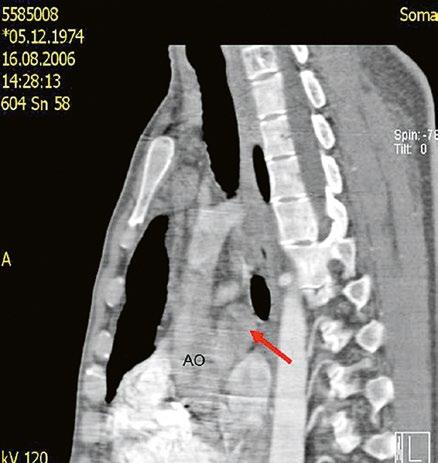

Supravalvární pulmonální stenóza a stenózy větví plicnice bývají součástí komplexních VSV (např. Fallotovy tetralogie) nebo syndromů (Williamsův syndrom, syndrom Noonanové, syndrom vrozené rubeoly, Alagillův syndrom aj.) (Obr. 45.39). Získané stenózy větví plicnice, ale i úplný uzávěr větve plicnice můžeme vidět po spojkových operacích podle BlalockaTaussigové (Obr. 45.40, Obr. 45.41). Pro zobrazení supravalvárních a periferních stenóz plicnice je optimální CT angiografie (Obr. 45.40, Obr. 45.41, Obr. 45.42, Obr. 45.43).

Obr. 45.43 CT angiografie, šipkou označena významná odstupová stenóza levé větve plicnice (LPA), lehčí stenóza odstupu pravé větve plicnice (RPA), kalcifikace v oblasti pulmonální chlopně